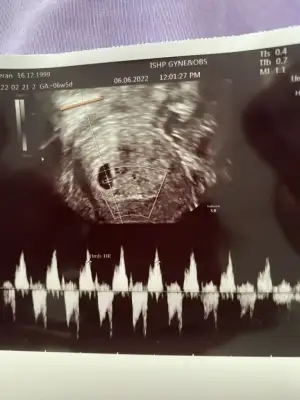

Benim için de tahmin yapar mısın 6+1 ve 7+4 ultrasonlar

Eklentiler

• 597745.webp

597745.webp

11,4 KB · Görüntüleme: 66

• 597744.webp

597744.webp

10,8 KB · Görüntüleme: 65